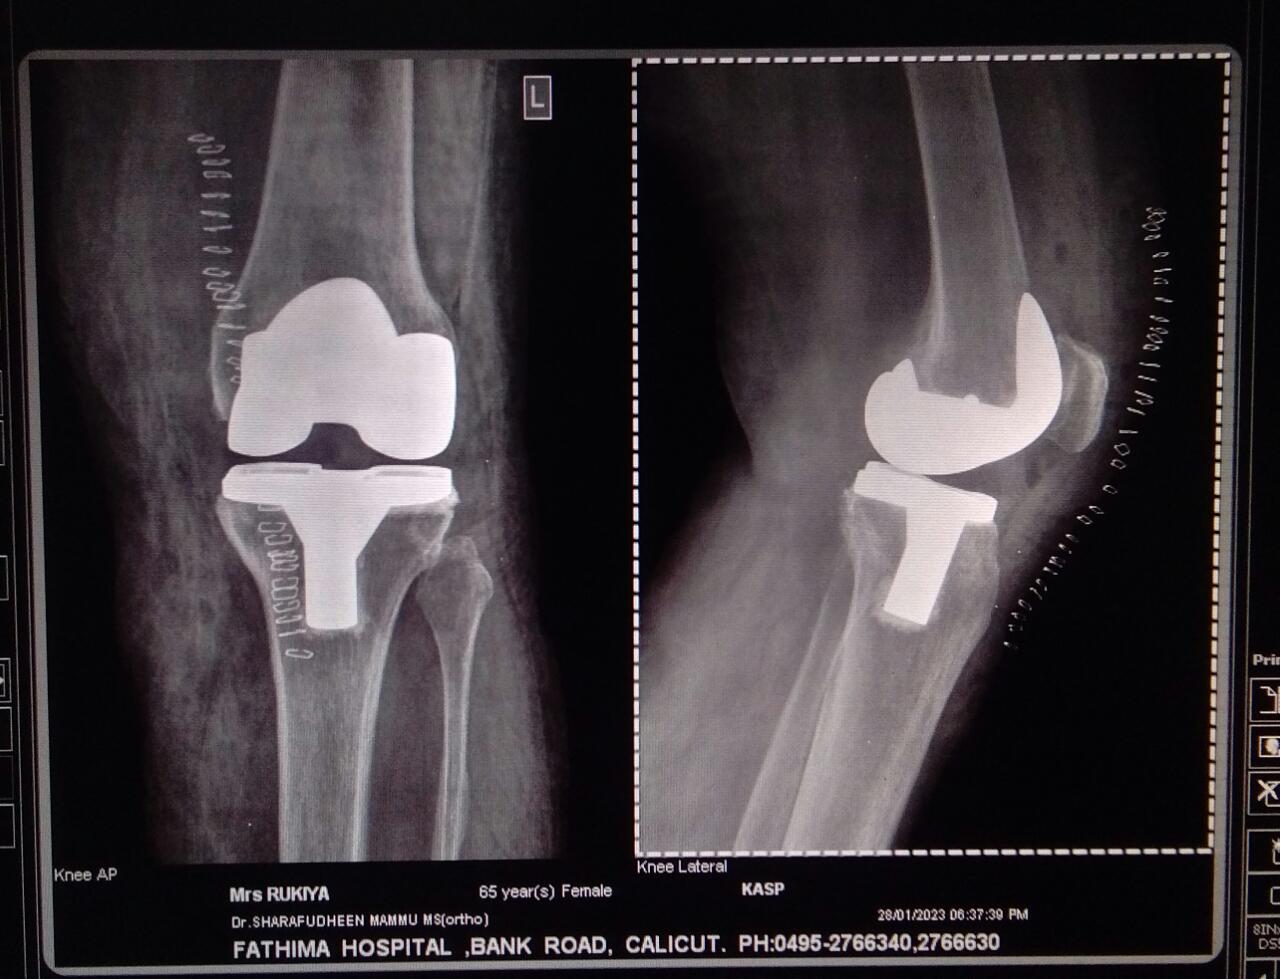

Knee and Hip Replacement